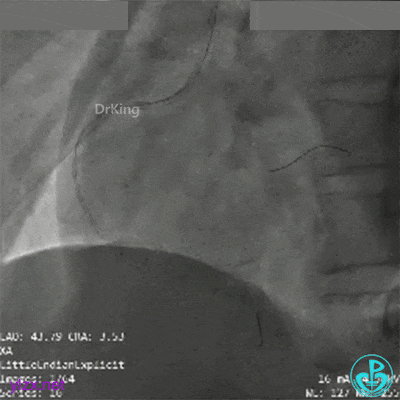

冠脉造影

RCA第一转折50%狭窄,第二转折前100%闭塞。